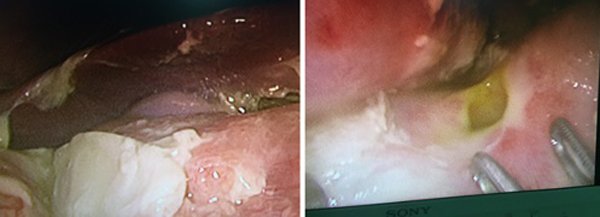

Bệnh nhi nhập viện trong tình trạng đau bụng dữ dội vùng trên rốn, trước đó từng nôn ra máu. Khi chụp CT ổ bụng,...